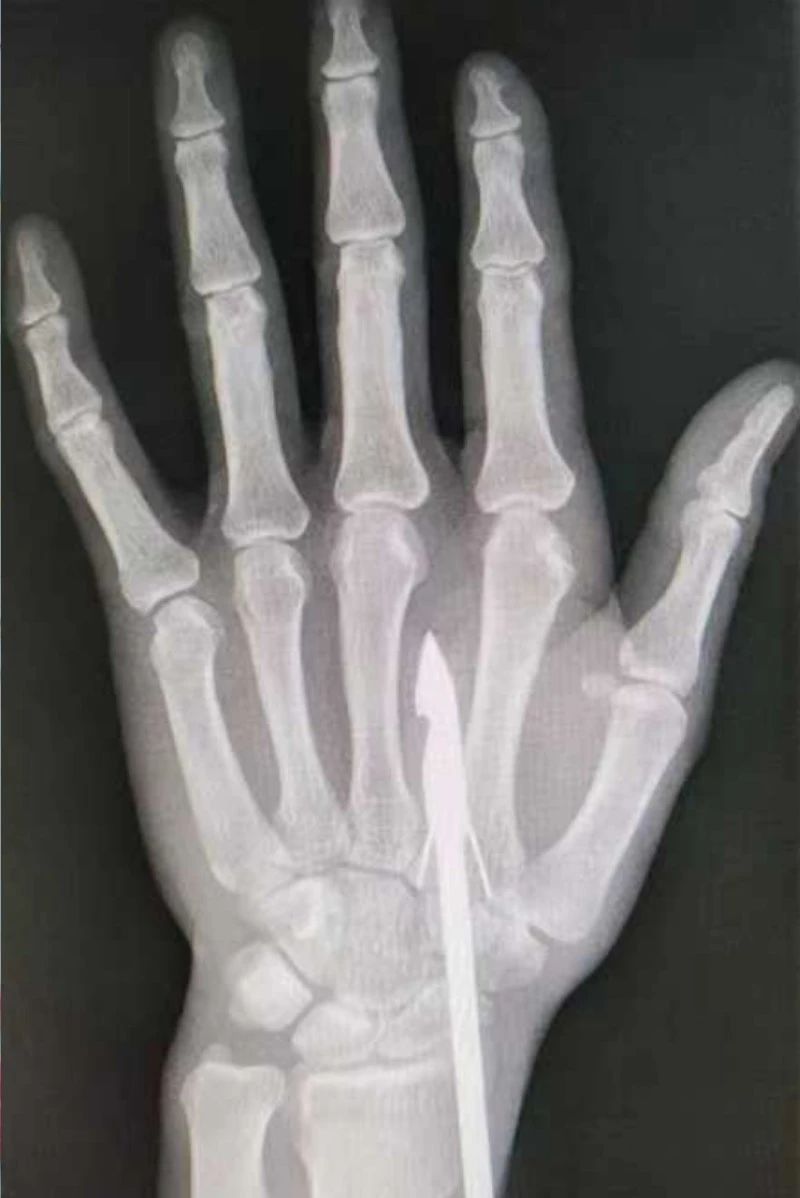

時間緊迫,每一秒的流逝都可能對傷者的手部功能造成不可逆的損害。接診醫生代彭威,迅速對傷者進行了初步檢查。他注意到,魚鉤已經深深嵌入皮膚,情況遠比表面看起來復雜。沒有絲毫猶豫,立即安排了X線檢查以確認魚鉤的位置及傷及范圍,以及急診化驗檢查以評估患者的整體狀況。

確保在取出魚鉤的同時,不對周圍的組織造成額外的傷害。8點15分左右患者在局部浸潤麻下進行手術,經探查后魚鉤未傷及重要血管、神經及肌腱,經過緊張的十分鐘,魚鉤終于被順利取出,隨后對傷口進行了仔細的清理和縫合,用敷料仔細包扎,確保傷口能夠順利愈合。